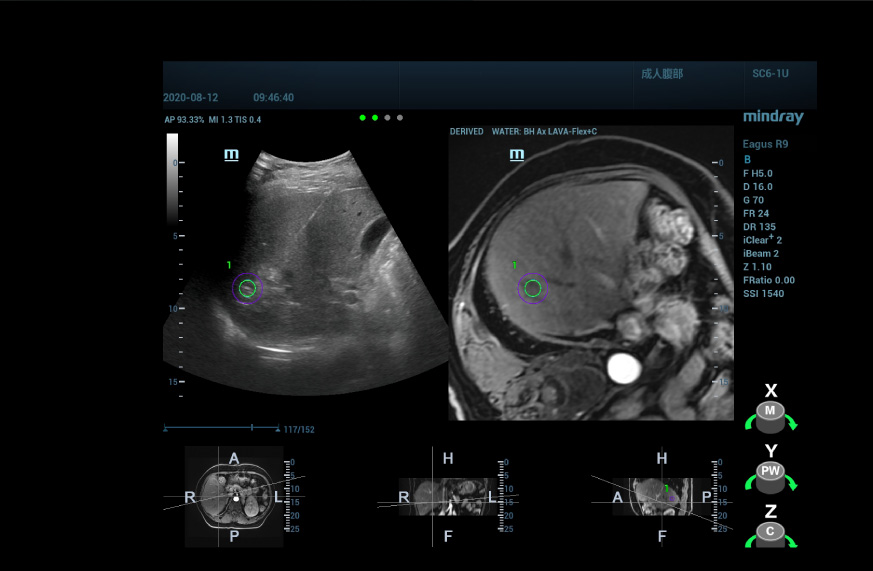

Ge?nspireerd door het idee, begonnen prof. Xie en haar team te zoeken naar manieren om een navigeerbare 'kaart' te maken om de tumor te positioneren. Ze ontdekten dat multimodaliteitsfusie tussen realtime echografie en een kaart gemaakt van CT al was gebruikt bij behandelingsbegeleiding. Maar aangezien CT een omslachtig proces is, bestond er misschien een mogelijkheid om echografie te gebruiken om de laesie in kaart te brengen?

Door gebruik te maken van een multimodale fusietechniek, kan uHit Fusion van Mindray de MRI-informatie fuseren met het ultrasone beeld, zodat we de locatie kunnen zien van abnormaal versterkte knobbeltjes die door de MRI T1WI-versterking worden getoond. Met de aanvullende informatie over ruimtelijke positionering, naast de MRI, zijn we in staat om de laesie met een hoge mate van zekerheid te lokaliseren.

Voor het ultrasone/echografische fusiebeeld verkrijgen we 3D-echografiegegevens van de laesie v├│├│r de procedure en fuseren we deze met het realtime 2D-beeld, zodat de informatie van de beoordeling v├│├│r de procedure volledig kan worden benut, en de locatie en aard van de laesie kunnen worden bevestigd door opnieuw echografie uit te voeren.